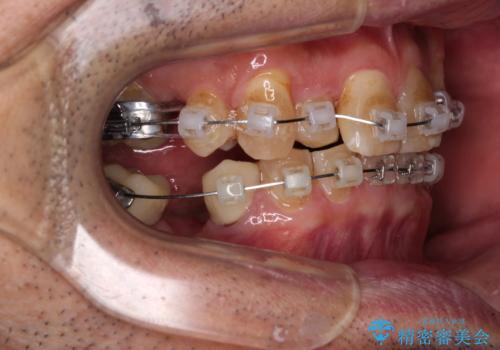

奥歯の欠損と前歯のデコボコを治したい インプラントと矯正治療の総合歯科治療

- 下顎両側の欠損と上顎前歯のデコボコを気にして来院された患者様です。

デコボコは今まで気にせずにいたそうですが、奥歯の欠損改善を機に、矯正治療に興味があるので、相談したいとのことでした。

奥歯に欠損が多く、矯正治療はやや難航することが予想されますが、患者様の希望もあり、上顎左右小臼歯を1本ずつ抜歯し、ワイヤー装置にて矯正治療を行うこととしました。

矯正歯科治療を行うに当たり、痛みや違和感を感じている歯の根管治療を行い、矯正治療中にインプラント埋入し、補綴治療と矯正治療を同時に終了できるように進めて行くこととしました。